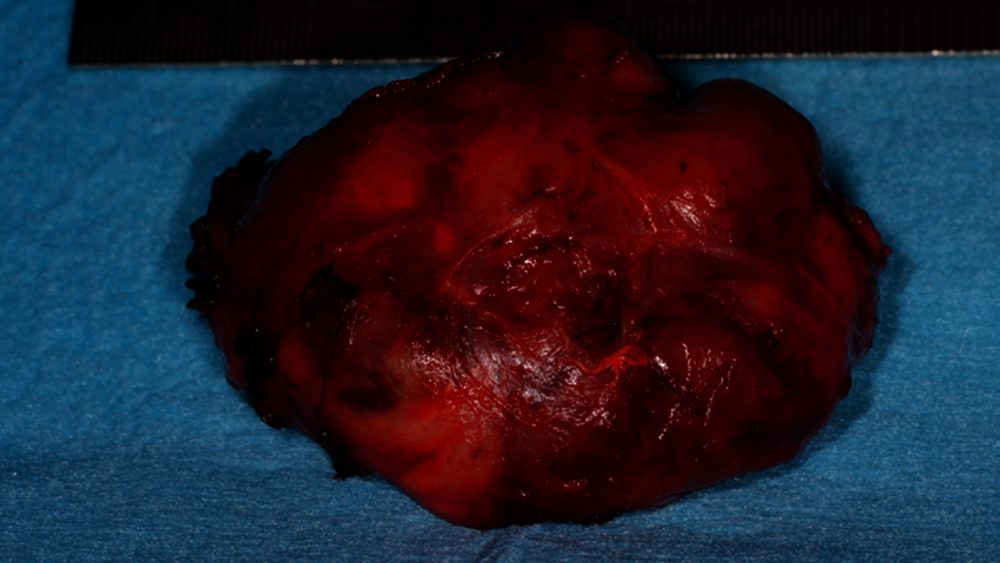

In Anbetracht des weiterhin unklaren Prozesses wurde die Indikation zur operativen Resektion des Tumors gestellt. Unter Intubationsnarkose erfolgte die Inzision parallel zum Ductus parotideus. Unmittelbar transmukosal konnte bereits die Kapsel der Raumforderung dargestellt und der Befund stumpf herausgelöst werden. Nach Entfernung des Tumors zeigte sich die direkte Lagebeziehung zum Ramus mandibulae und zu den Temporalisfasern ebenso wie retrotubär (Abbildung 4).

Die histopathologische Aufarbeitung des Exzidats zeigte makroskopisch einen glatt membranär überzogenen 4 cm x 3,4 cm x 1,5 cm messenden Befund mit beiger, partiell zystisch transformierter Schnittfläche. Mikroskopisch konnte ein knotiges, zellreiches, überwiegend solide und fokal zystisch wirkendes Proliferat beobachtet werden. Die immunhistochemischen Untersuchungen ergaben eine spezifische Reaktion auf CD34, allerdings eine Negativität auf S100. Der Proliferationsindex lag bei 10 bis 15 Prozent; es wurden 5 Mitosen pro 10 high power field (HPF) beobachtet.